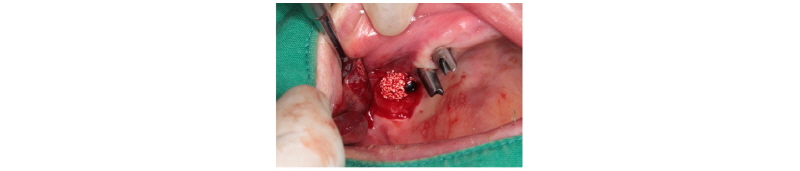

앞서 설명한 것처럼, 통상 metal sleeve와 drill 사이의 gap, 공차 혹은 유격이 존재하는데, guide 제작 회사마다 다르다(Fig. 42, 43). Park 등5에 의하면, 각 회사별 공차를 연구했는데, 단순히 숫자의 비교로 각 시스템의 우열을 판가름하기 어렵다고 한다. 즉, 수술 시 부드러운 drilling에 따른 편의성의 측면(공차가 상대적으로 큼)과 guide의 정확도의 측면(공차가 상대적으로 작음)에서, 어느 쪽에 치중할지에 대한 견해의 차이일 뿐이라고 한다. 그렇지만 이것은 중요한 사안이라고 봐야 한다. 자세히 내용을 살펴보면, initial drill, 2.0 mm twist drill, fixture mount 등 모든 drill과 metal sleeve 사이의 유격으로 인해서 그 drill이 기울어지는 각도들의 평균값을 보여준 것이다. 2.0 mm drill 사용 시 각도가 틀어짐으로 해서 나타나는 drill tip의 변위가 apex에서 최대 3 mm가 될 수 있으므로 주의를 요한다. 해당 연구에서의 결과에서 보듯, 아주 중요한 사안이 될 수밖에 없다. 즉, path가 기울어짐으로써 잘못된 drilling으로 인해 우리가 계획한 것이 아닌 잘못된 위치에 implant를 식립할 위험이 있다는 것이다. 해당 증례는 헐거운 metal sleeve를 통해 #i47 drilling 과정에서 기존 drill path에서 어긋나기 시작하여 fixture 식립할 때 하악 구치부 치밀골 하방의 해면골로 빠졌다(Fig. 44).

Fig. 44. (Left) Surgical failure can occur if the path is not well maintained through the drilling sequence. In this case, metal sleeve of surgical guide cannot offer an advantage for flapless implant surgery. Consequently, the mispath lead #i47 implant fixture to go too far away. (Right) Implant fixture on #i47 area was explanted, fortunately leaving no nerve damage. |